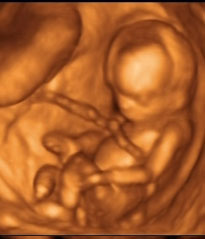

És most értünk meg igazán arra, hogy gyermeket várjunk...